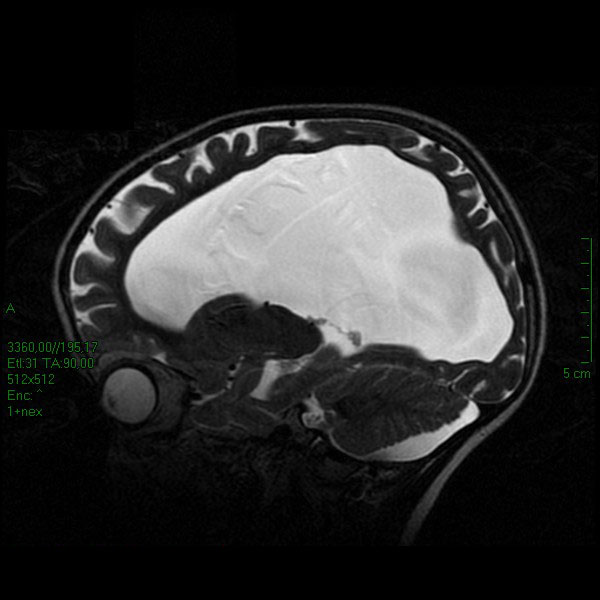

Alla valutazione neuropsichiatrica non si documenta ritardo cognitivo, mentre viene descritta una condizione di fragilit� emozionale. Emma viene quindi sottoposta a intervento di terzoventricolostomia per via endoscopica. Il decorso postoperatorio � stato regolare, in assenza di deficit neurologici. Dopo 4 mesi dall�intervento le dimensioni del terzo ventricolo appaiono lievemente ridotte e si evidenzia una minima riduzione di volume anche dei ventricoli laterali (Figura 3).

Figura 3. Immagine RMN post-intervento